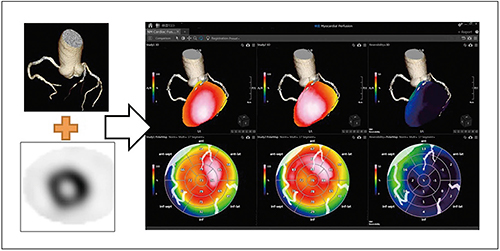

●冠動脈CT画像と心筋SPECTのフュージョン“NM Cardiac Fusion”

近年,ソフトウエアの進歩により,冠動脈の形態的評価を行う冠動脈CT画像と機能的評価を行う心筋血流SPECTをフュージョンさせる手法が開発されており,その融合画像は臨床の場で高く評価されている4),5)。

GCA-9300Rに搭載されるNM Cardiac Fusionも画像フュージョン用アプリケーションの一つで,冠動脈CT画像とSPECT画像の3Dフュージョン表示が可能である。冠動脈の状態(走行・狭窄や石灰化の有無)と心筋血流の状態(虚血・梗塞の有無)を同時に観察することで,責任血管の判定,治療方針の決定,被検者への説明に効果が大いに期待できる(図8)。

また,本アプリケーションでは,ポーラーマップ解析画像も冠動脈CT画像とフュージョン可能で,被検者自身の冠動脈CT画像をオーバーレイ表示することで複雑な血管走行をポーラーマップ解析画像上でも容易に把握できる。もちろん,ポーラーマップ解析はreversibilityやwashoutといった各種の解析に対応している。

図8 NM Cardiac Fusion使用画像

(画像ご提供:鹿児島大学様)